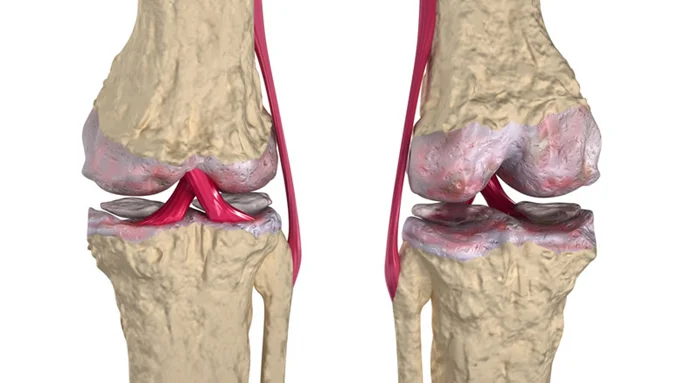

6. Костные инфекции и разрушение суставов

Боль – это не просто неприятное ощущение. Это сигнал, что с телом что-то не так. Без этого сигнала организм становится уязвимым для различных инфекций и заболеваний. Люди с ВНБ часто страдают от хронических костных инфекций (остеомиелита) и разрушения суставов (артропатии Шарко). Почему? Да потому что переломы и травмы, которые они не чувствуют, становятся воротами для инфекций. А поврежденные суставы, без "болевой защиты", быстро изнашиваются и разрушаются.